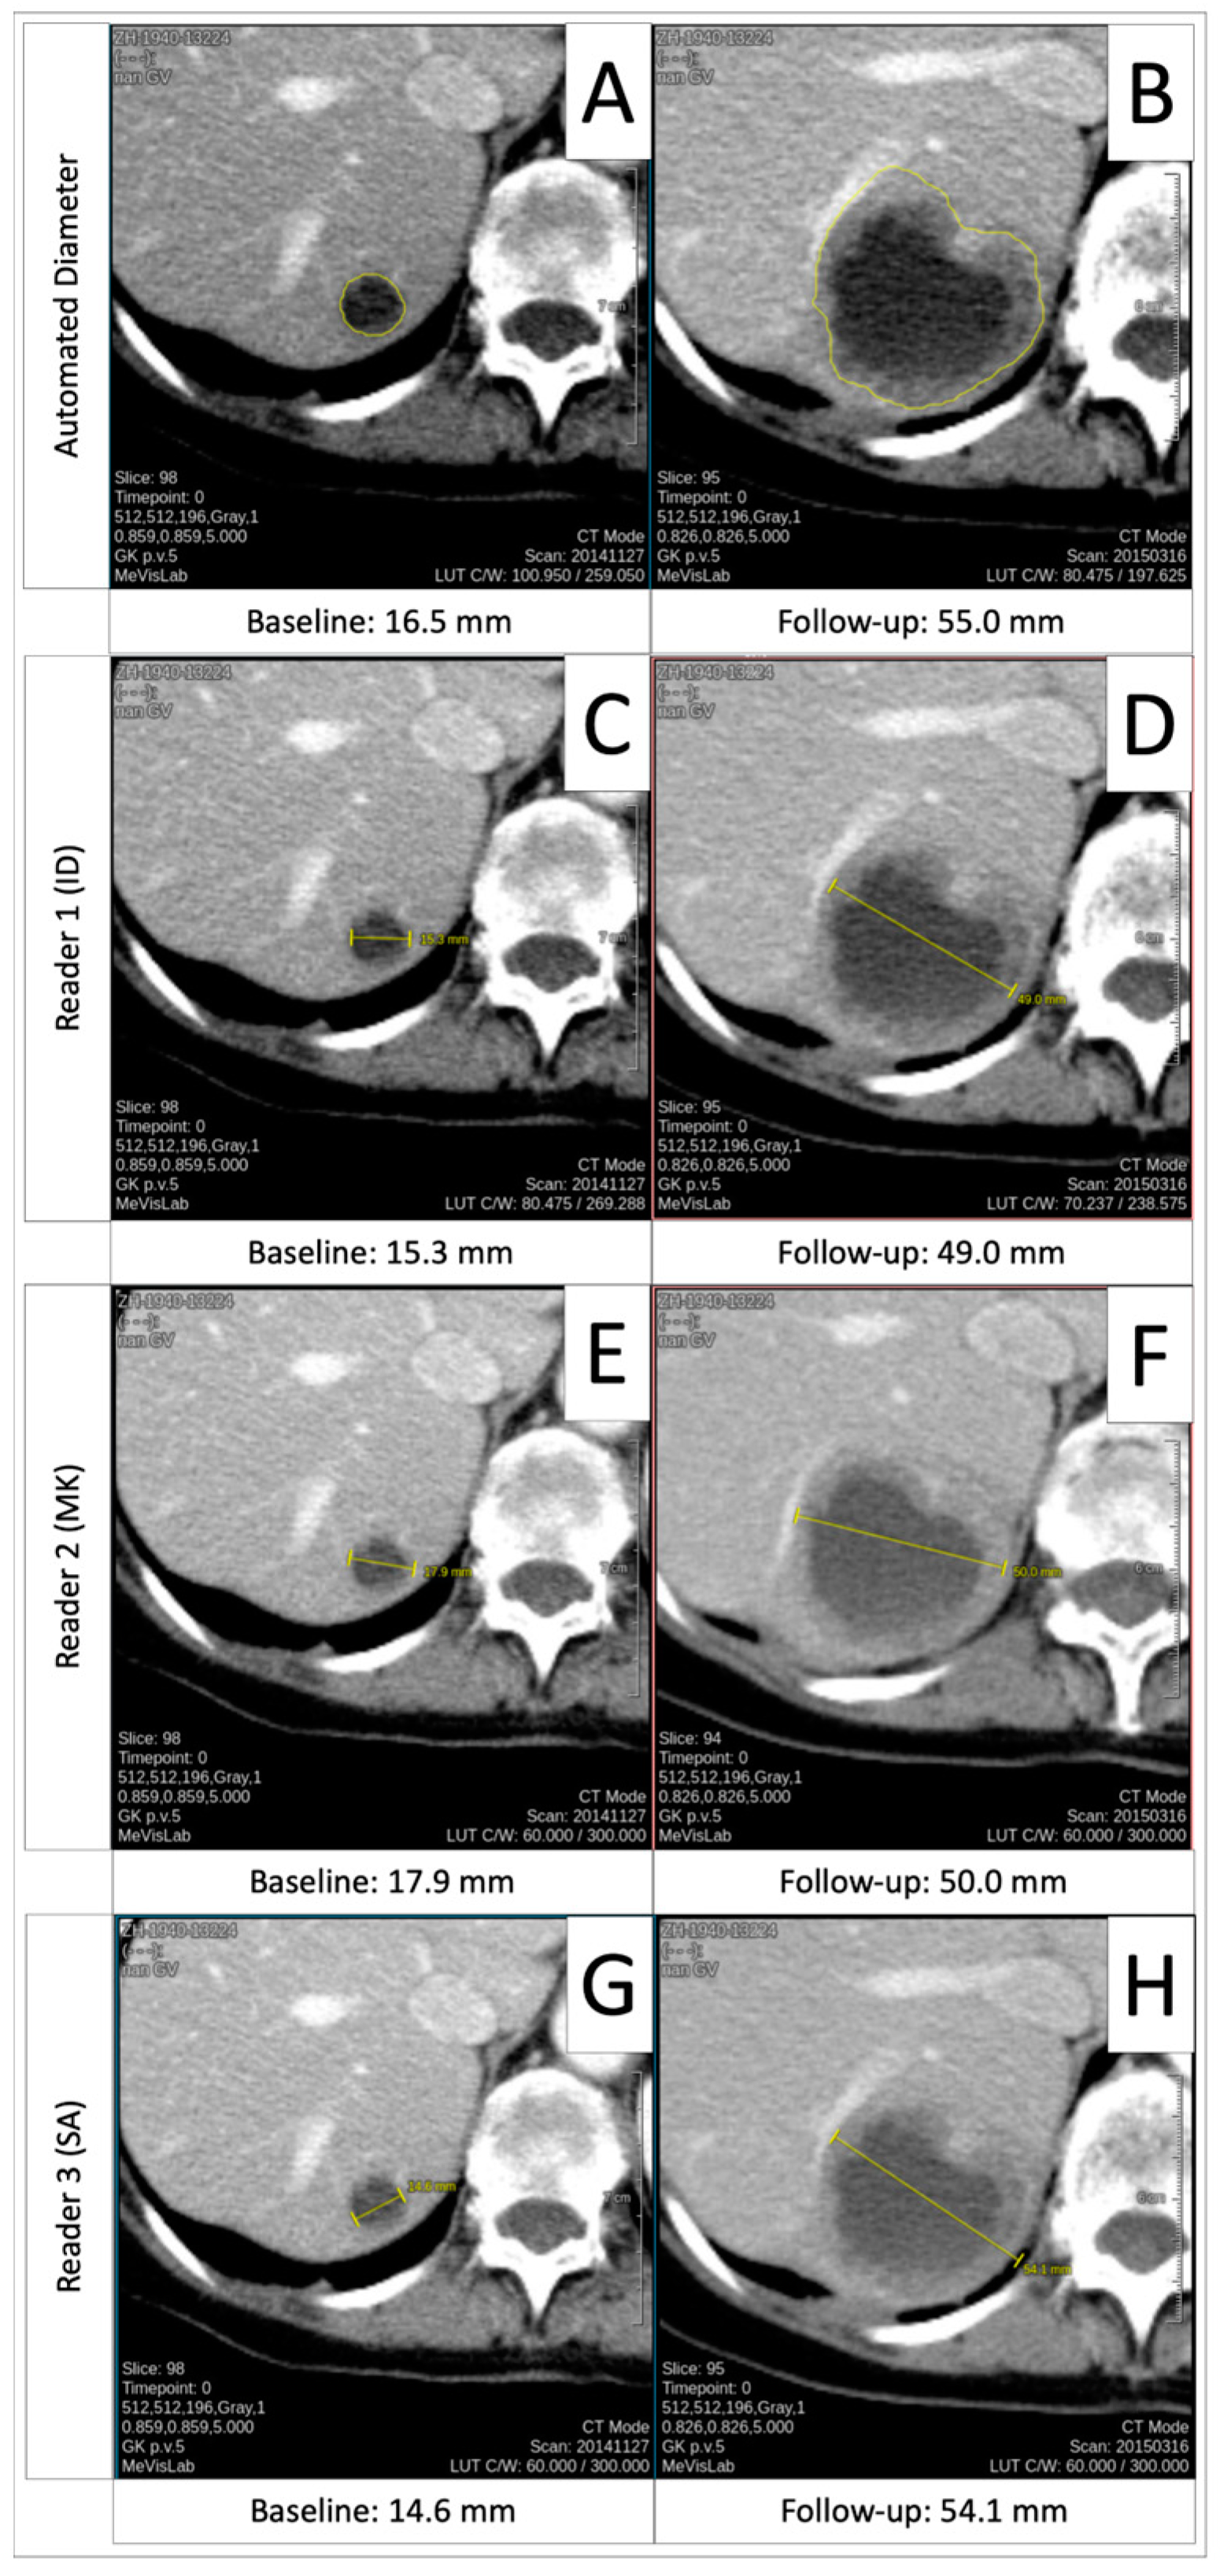

3.6. Progressive Disease Timepoint Response Deviation